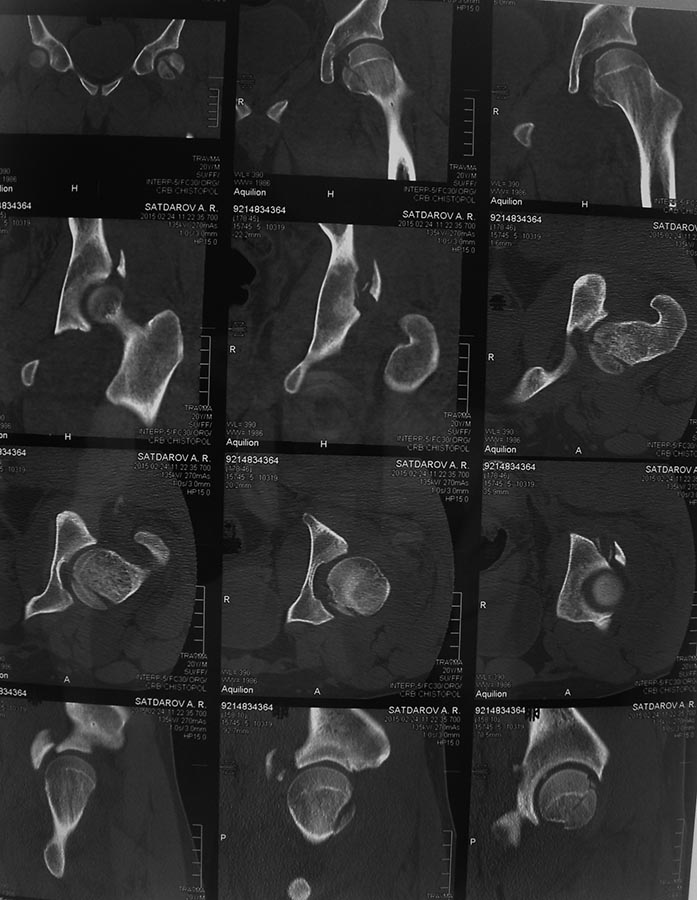

Случай практически идентичный описанный в январе 2015 на ортофоруме Никитой Николаевичем Заднепровским. Молодой человек 20 лет ДТП 23.02.2015, Диагноз: Сочетанная травма. Закрытый переломо-вывих головки и перелом заднего края вертлужной впадины (Pipkin4) правой бедренной кости. Открытый подтаранный вывих правой стопы. При поступлении в ЦРБ вправление вывиха головки бедра и подтаранного вывиха стопы.

Далее перевод к нам в Травмоцентр и 03.03.2015. через 8 дней операция, выполнен остеосинтез головки 3-мя самокомпрессирующими винтами Autofix под разными углами с погружением в субхондральный слой. Доступ Kocher-Langenbeck с флип-остеотомией большого вертела и задним хирургическим вывихом головки бедра. В полости сустава два свободно-лежачих фрагмента хряща головки, которые были удалены. На снимках виден дефект хряща головки после репозиции. Небольшой фрагмент заднего края фиксирован двумя спонгиозными винтами. Далее шов раны с дренированием. На 2 сутки пациент поворачивался на здоровый бок с валиком между ног, на 4 сутки сидел в кровати и на 6 сутки ходил с помощью костылей.